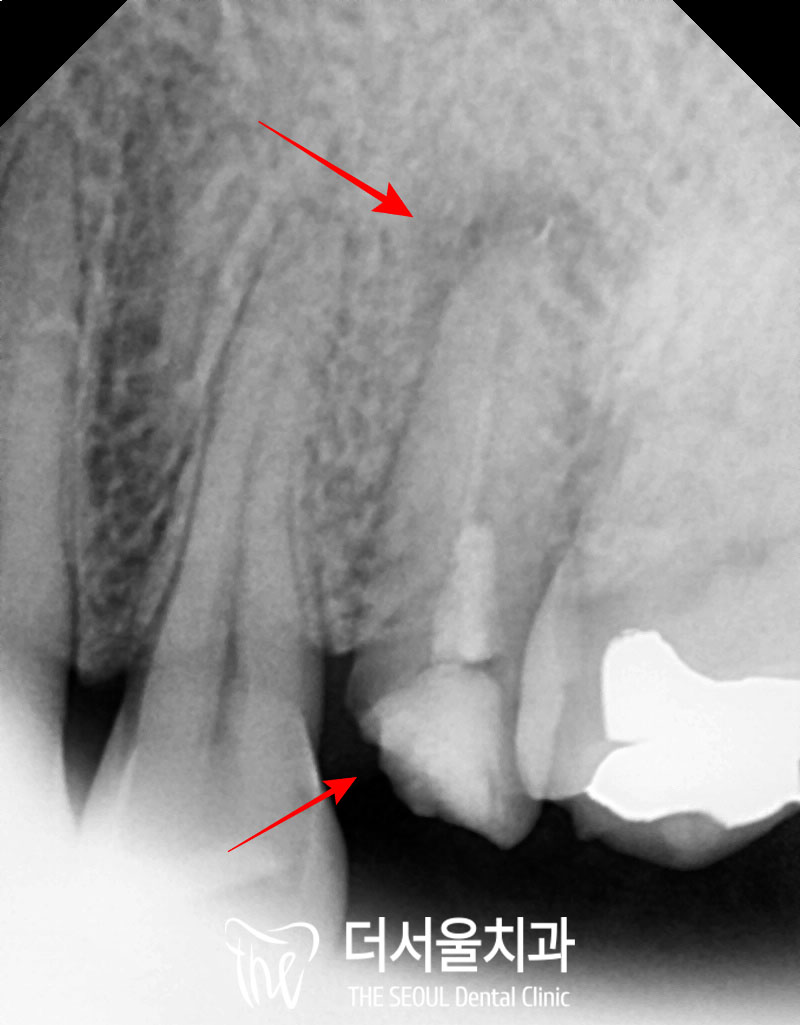

검진을 받으러 오셨을 당시

왼쪽 위 신경치료 후 크라운을 씌워놓은

두 번째 작은 어금니(#25) 뿌리 부근에

염증 소견이 있기도 하고,

구강을 살펴보면

크라운과 치관이 떨어져 나간 채로

뿌리만 잇몸에 남아있었습니다.

깨진 양이 많고,

이전에 신경치료를 받았던 이라

이미 수명이 짧아진 채로 약해져있었기에

해당 치아는 발치 후 임플란트를 해야겠습니다.